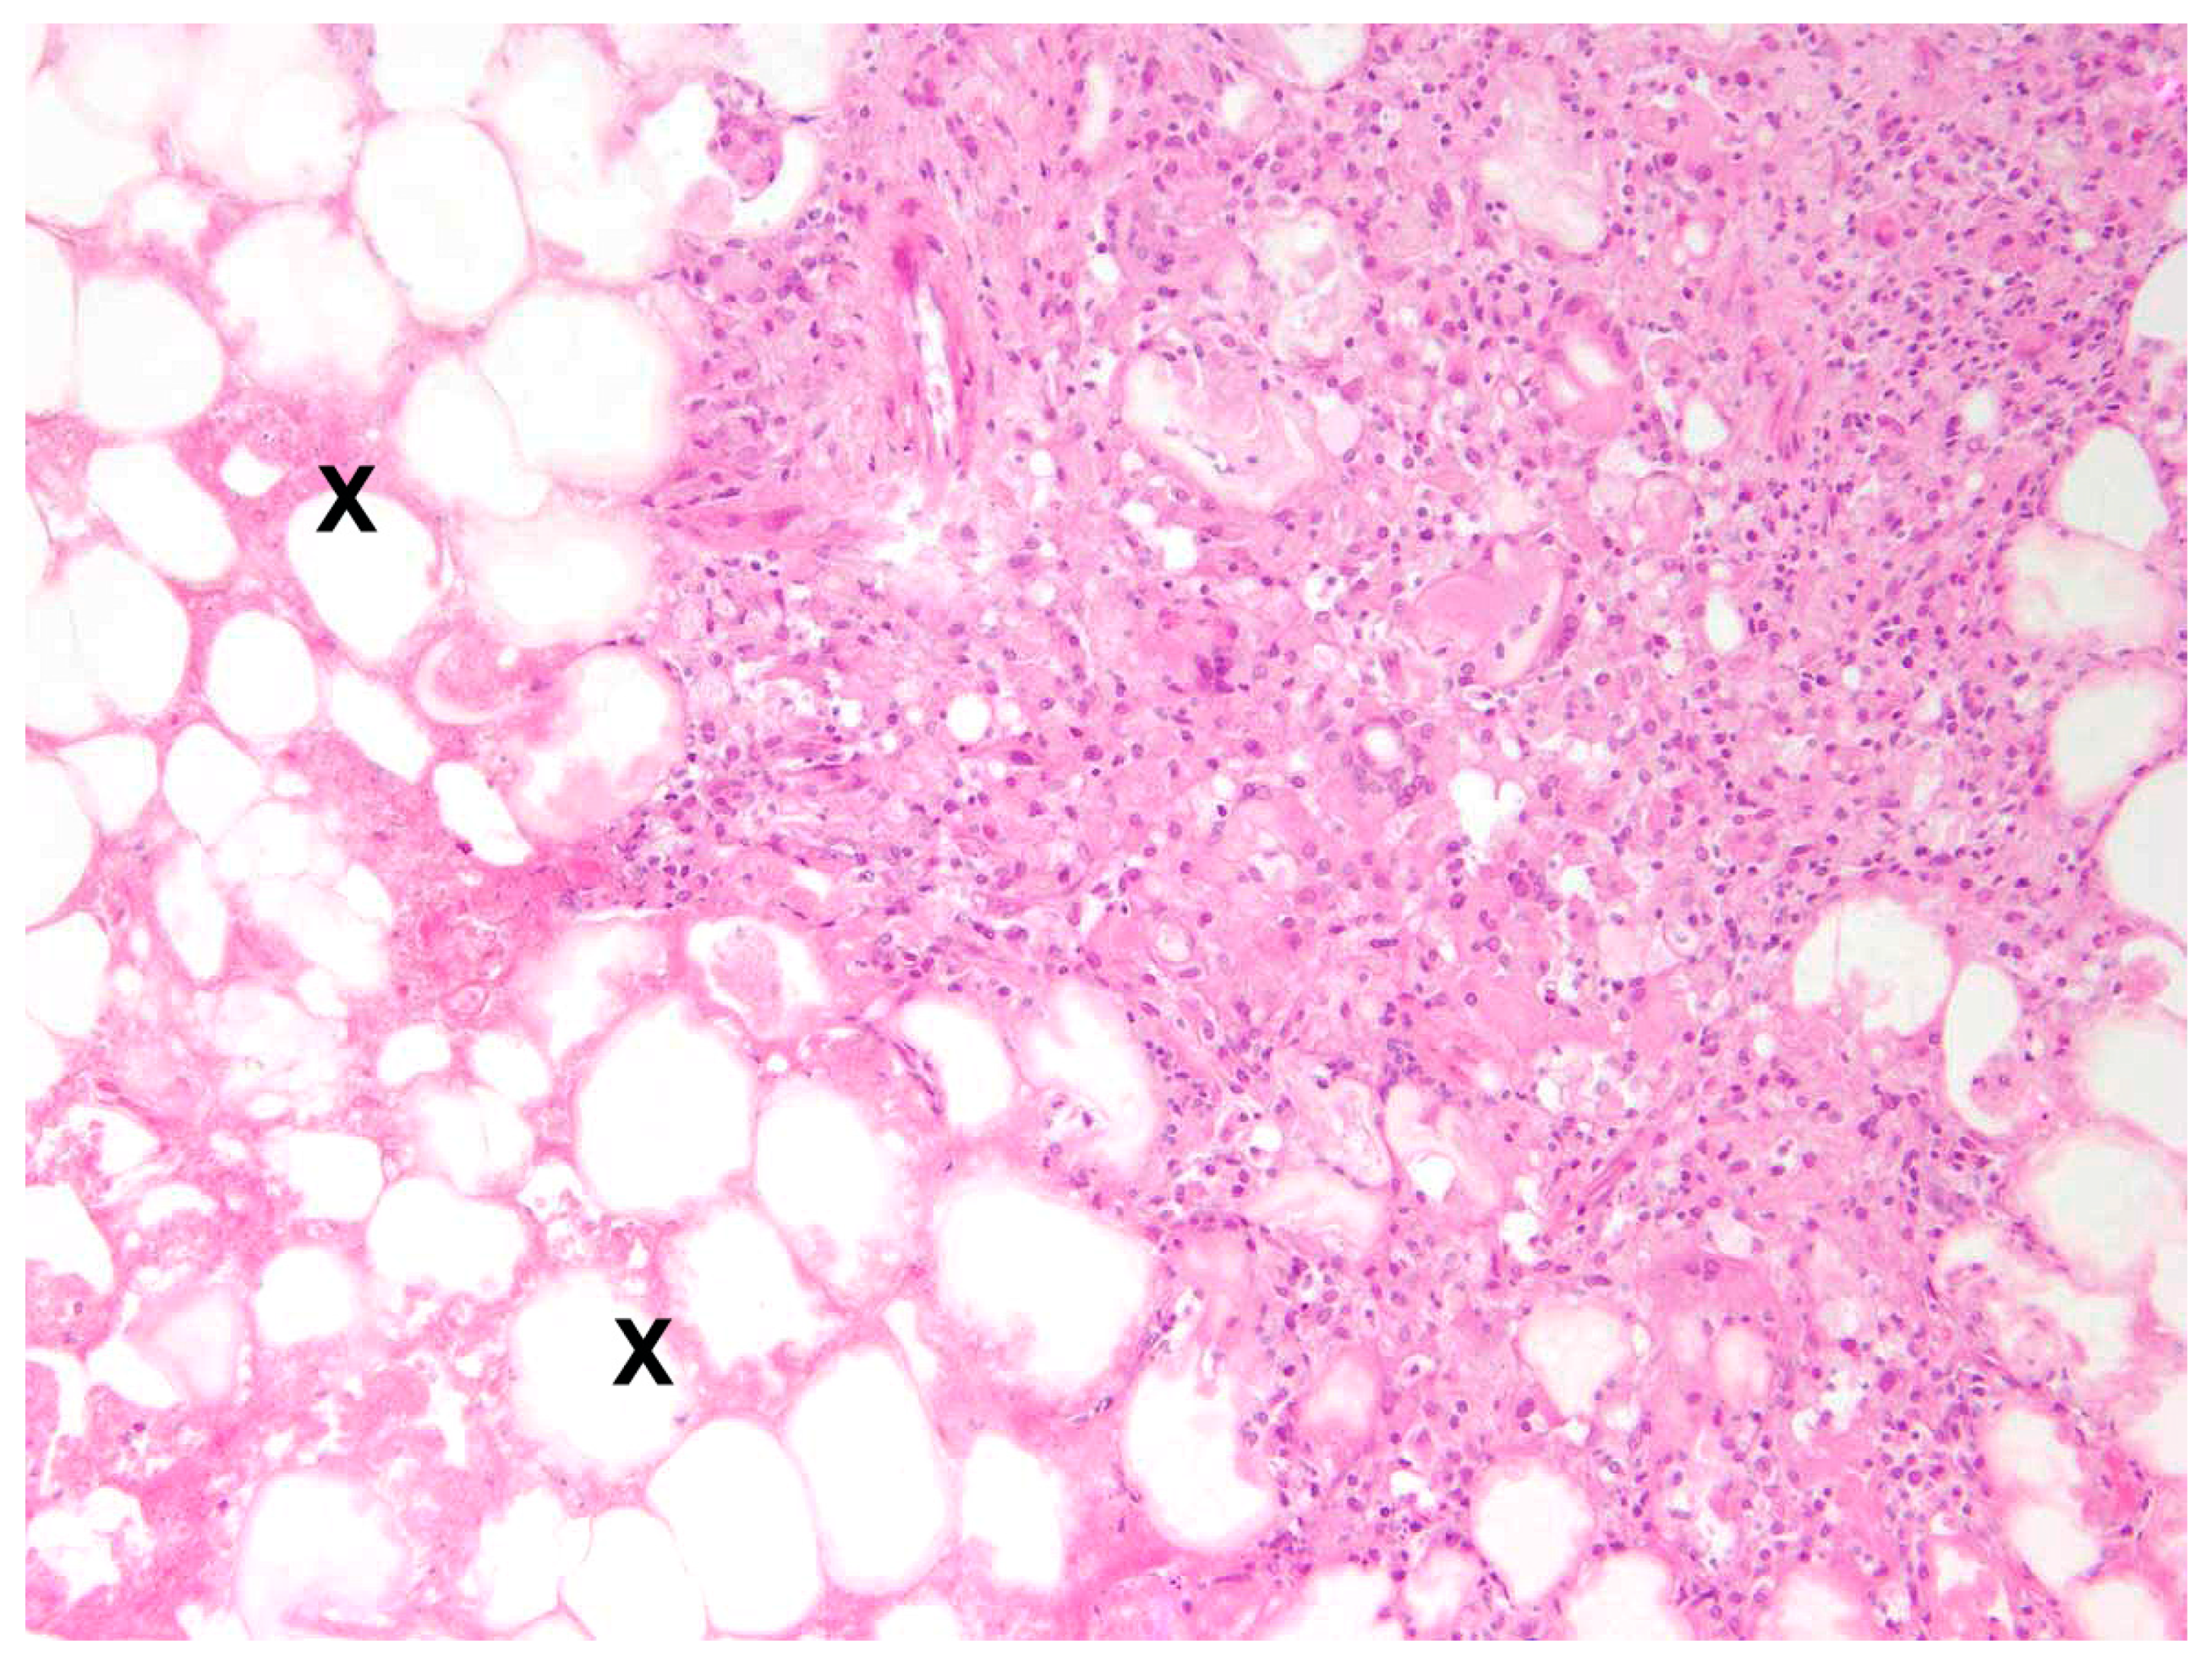

The main type of hepatitis was non-purulent with different proportions of lymphocytes, plasma cells, and macrophages (93.0%, n = 80; Figure 4), followed by purulent (14.0%, n = 12), necrotising (5.8%, n = 5), and granulomatous type (5.8%, n = 5). Eight cases (9.3%) of hepatitis showed a mixed inflammatory type.

In 88.9% (n = 32) of cases, steatitis was granulomatous, including 31 cases (86.1%) of granulomatous to necrotising steatitis (Figure 9).

All inflammations of the kidneys were non-purulent, with interstitial infiltrations of lymphocytes, macrophages, and plasma cells (Figure 12). In one adult male, fibrosis and depression on the kidney surface were observed.